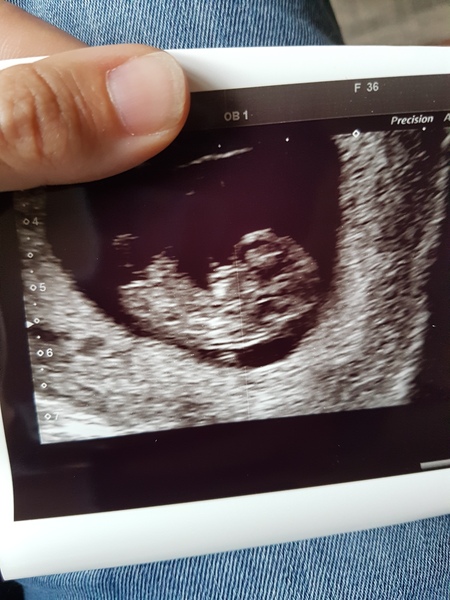

SS81C · 02/08/2017 16:01

One tiny fuzzy bean on USS. I'm a few days ahead of what I thought so my EDD is 28th Feb. Drank way too much water and the sonographer made me empty half of my bladder. Got another scan in 3 weeks for nuchal as too early today.

@SS81C bean looking good there :)

Scan went well today measuring a day ahead today so 8 +1 weeks. I think I'll wait and see at my 12 week scan though for the 'official' due date. I'm starting to get excited now. We got a picture today so it feels real. I'm calling my gphone tomorrow to finally register with a midwife. I've been putting it off until now not to tempt fate!

Scan all good! Heartbeat measuring 168bpm and I've moved forward a few days to 8+2 by today's measurement, though I think I'll stick with my dates of 7+6 until the 12 week scan :)

Hometown I had a scan at 8+5 this time. It was reassuring to see the heartbeat, but felt a bit of an anticlimax other than that and hasn't provided any longer term reassurance. It was £89 and lasted literally 5 minutes! It was nice to get a couple of pictures, but really was just a blob with a bigger head blob!